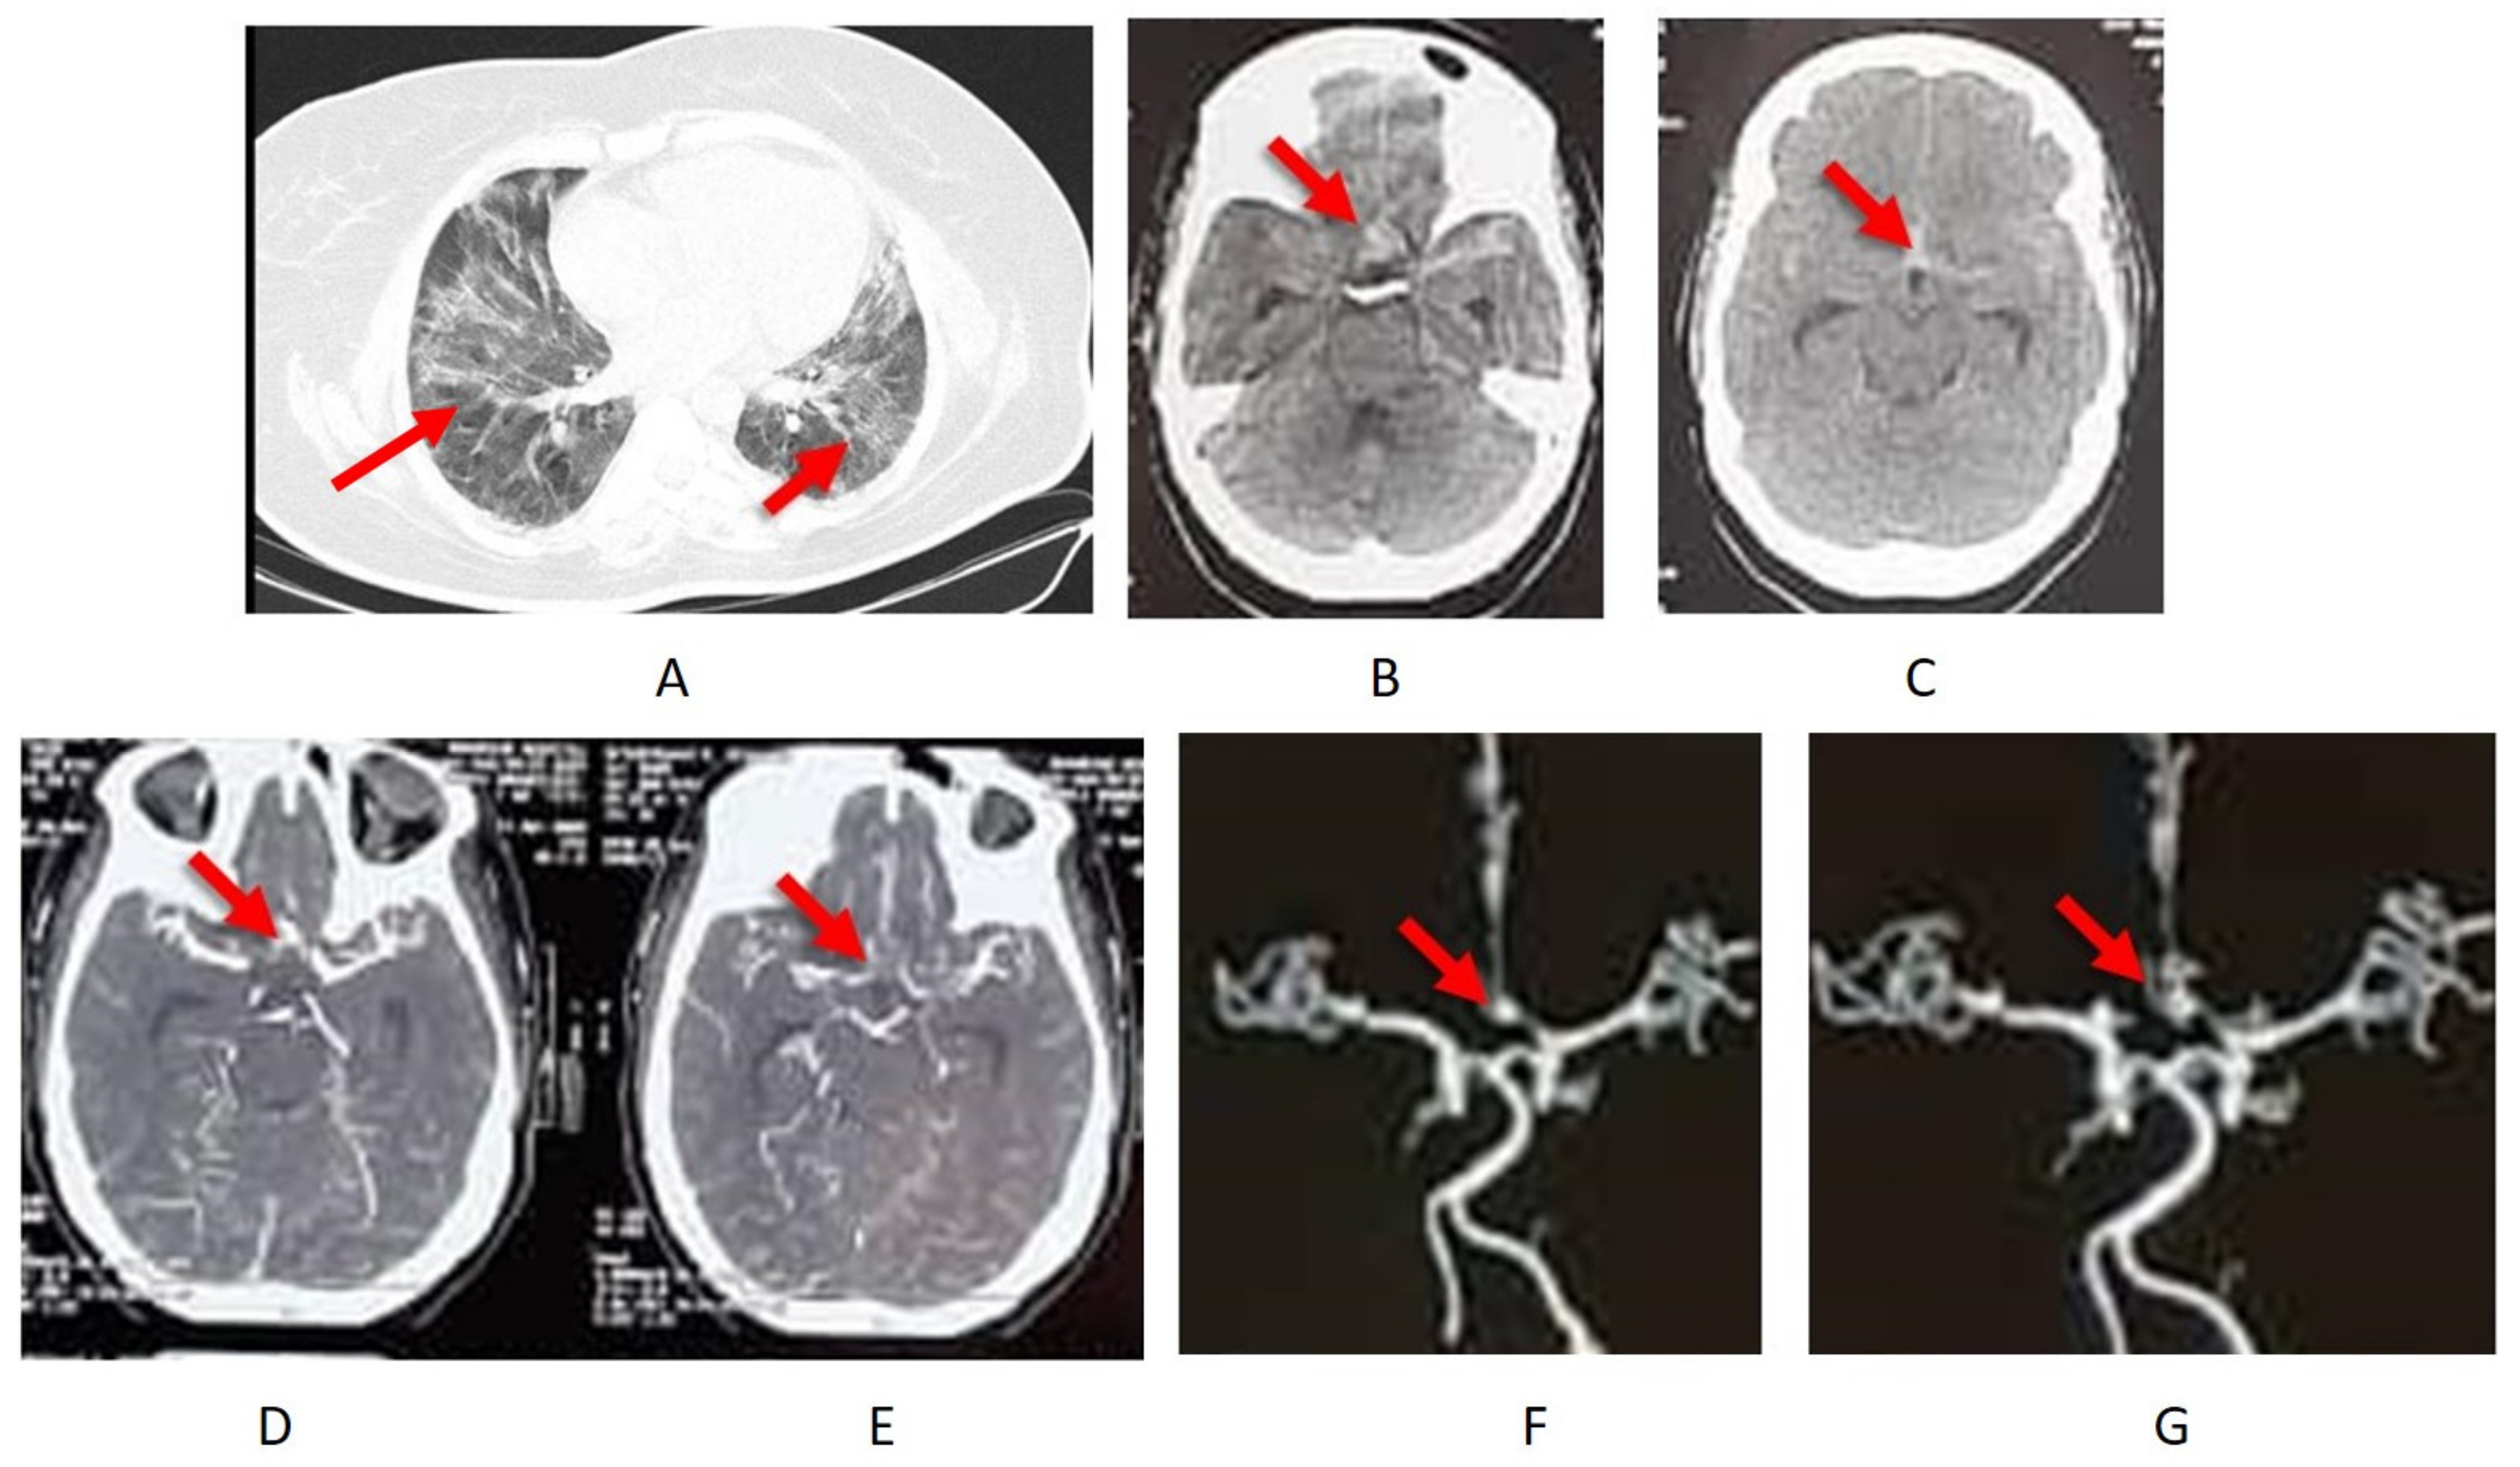

3. Results

4.4. Case Description

4.5. Treatment and Outcome